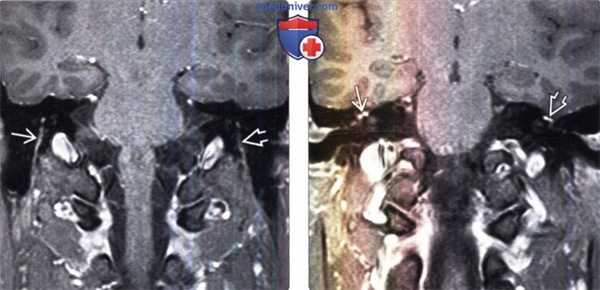

(Слева) МРТ, постконтрастное Т1-ВИ, режим подавления сигнала от жира, корональный срез: у пациента с правосторонним параличом Белла определяется выраженное асимметричное контрастирование сосцевидного сегмента правого ЧН VII по сравнению с минимальным контрастированием аналогичного участка ЧН VII слева.

(Справа) МРТ, постконтрастное Т-ВИ, режим подавления сигнала от жира, корональный срез: у этого же пациента определяется схожий характер контрастирования правого коленчатого ганглия по сравнению с левым. Это наблюдение можно объяснить тем, что коленчатый ганглий, наряду с задним коленом/верхним сосцевидным сегментом лицевого нерва могут контрастроваться и в норме.

(Слева) При корональной МРТ Т1 ВИ С+ FS у пациента с правосторонним параличом Белла определяется асимметричное интенсивное контрастирование сосцевидною сегмента ЧН VII справа по сравнению с минимальным контрастированием слева.

(Справа) При корональной MPT Т1 ВИ С+ FS у этою же пациента определяется аналогичное контрастное усиление правою коленчатою ганглия по сравнению с левым. Это можно объяснить тем фактом, что коленчатый ганглий, как и заднее колено/верхний сосцевидный сегмент лицевою нерва могут в норме накапливать контраст.